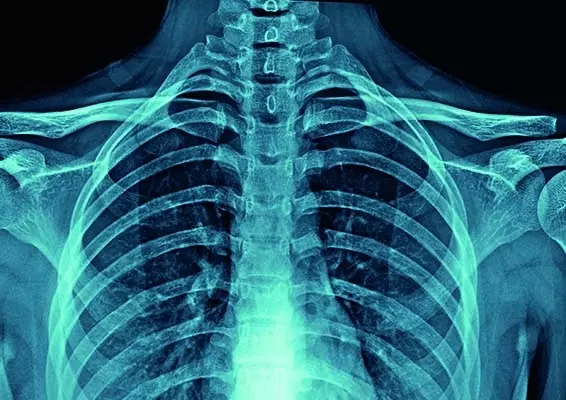

PROMIENIOWANE RTG W PRAKTYCE FIZJOTERAPEUTYCZNEJ

Promieniowanie radiologiczne (RTG) jest złotym standardem diagnostyki obrazowej. Jest badaniem szybkim w wykonaniu, powszechnym i niedrogim, a ukazanie rzeczywistego obrazu układu kostnego daje mu atut, którym przewyższa nowoczesne badania diagnostyczne. Zastosowanie zarówno aparatów rentgenowskich, jak i innych diagnostycznych aparatów nieinwazyjnych ma swoje zasady, cele i wzajemnie się uzupełnia. Należy pamiętać, w jakich sytuacjach ich używać, aby wykluczyć czynnik szkodliwości w dojściu do celu, jakim jest diagnostyka pacjenta.